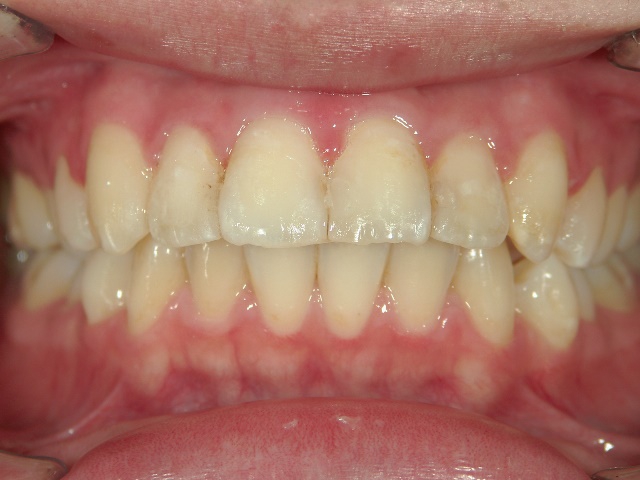

矯正歯科 治療前矯正歯科 治療前

矯正歯科 治療前

no.6_8296_治療前_右.jpgno.6_8296_治療前_正面.jpgno.6_8296_治療前_左.jpg